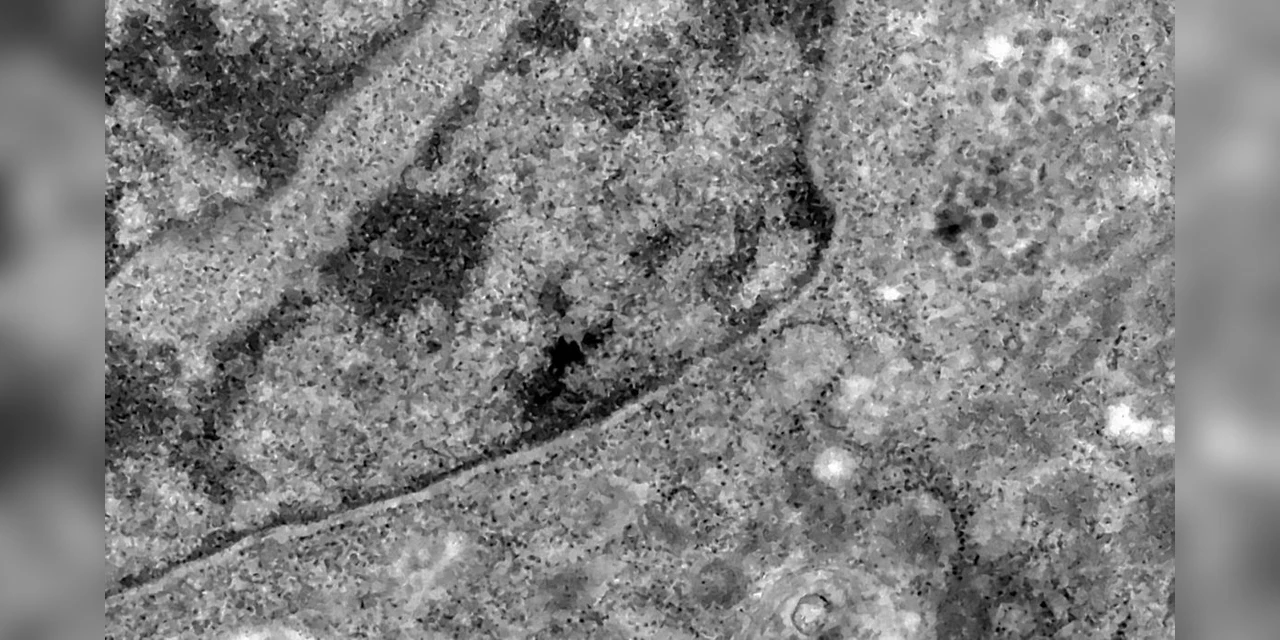

Os pesquisadores analisaram retinas de pacientes que morreram em decorrência da covid-19 e compararam com fotos dos olhos desses pacientes quando vivos para analisar as diferenças e formas de aferir a presença do vírus a partir da retina.

Segundo o professor da UFRJ e um dos coordenadores do estudo Rubens Belfort Jr, a retina é um biomarcador importante, pois faz parte do sistema nervoso, mas é mais acessível, permitindo identificar a presença do vírus em determinados locais do corpo, como nesse sistema.